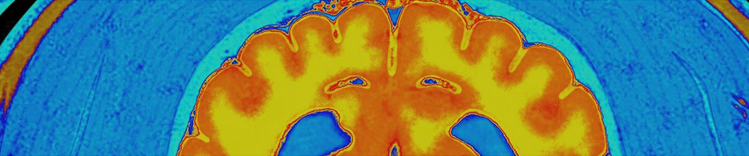

RESSONÂNCIA MAGNÉTICA

As mudanças físicas no cérebro associadas ao envelhecimento incluem:

- Atrofia (diminuição) do tecido cerebral de algumas regiões

- Aumento do volume ventricular

- Perda de neurônios e sinapses e redução na formação de novos neurônios

- Acúmulo de proteínas anormais